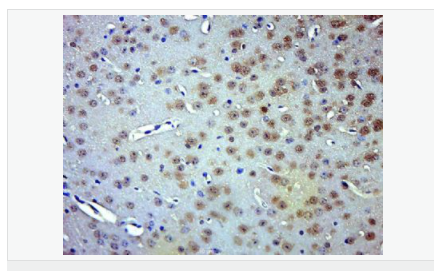

| 產品應用 | WB=1:500-2000 ELISA=1:5000-10000 IHC-P=1:100-500 IHC-F=1:100-500 Flow-Cyt=1ug/Test ICC=1:100 IF=1:100-500 (石蠟切片需做抗原修復) not yet tested in other applications. optimal dilutions/concentrations should be determined by the end user. |